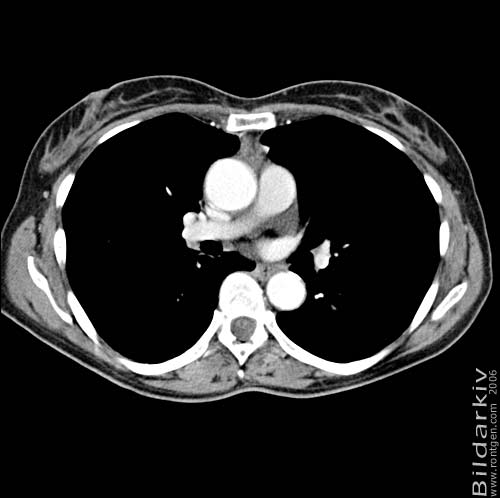

Snitt över thorax med kontrast. Sk. mediastinum-fönstersättning.

Mediastinum